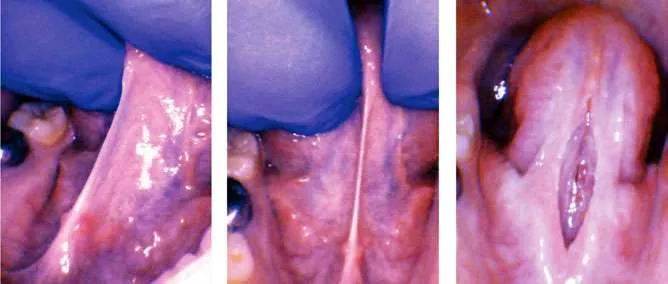

A nine-year-old autistic male patient who had trouble with speech, feeding, sleep, and reflux was presented by his mother for evaluation. His symptoms included frustration with communication, speech delay until age 5, poor speech intelligibility, chronic reflux since infancy, poor weight lifelong (4th percentile), and anterior loss of milk during bottle-feeding as a baby. Solid feeding had always been a challenge, and he was a “very slow eater.” He packed food in his cheeks “like a chipmunk”, choked and gagged on food, and spit food out frequently. His sleep quality and quantity were both poor according to his family. He had difficulty going to sleep, awakened easily and often, slept in strange positions, moved and kicked at night, ground his teeth, breathed orally at night, and snored often. His tongue-tie was a posterior tongue-tie and was therefore not recognized by his healthcare providers. It was not deemed to be a likely contributor to any of his issues previously (which is common in children with autism).

After a full history was obtained and all related symptoms, risks, and benefits of the procedure were discussed with his parents, they chose to have him undergo a lingual frenectomy. The instrument utilized was the 10,600 nm CO2 laser (LS-1005 LightScalpel, Bothell WA). The area was anesthetized with a compounded topical anesthetic, but neither nitrous oxide, oral sedation, general anesthesia, nor injected local anesthetic were used. A mouth prop was used, as well as two assistants to stabilize the patient, who was initially combative, but with the CO2 laser, the procedure was quick, and he calmed down even during the procedure itself. After 10 seconds of lasing at 3 W pulsed (Non-SuperPulse), 29 Hz, 72.5% duty (2.1 W avg), the tissue was vaporized with no bleeding or stitches, and minimal discomfort to the patient. The patient was instructed to perform oral exercises at home for three weeks postoperatively and the parents were shown how to do wound lifts if he would allow them. Two weeks later, the patient returned for a visit, and the mother reported that his “sleeping and eating improvement [had] been unreal.” It was easier for him to communicate, he was less frustrated when eating, his appetite had improved, he was swallowing more easily, he was finishing more of his meals, he was spitting food out less often, he was not gagging or choking on food at all, and he had less reflux. His sleep was also significantly improved. He fell asleep more easily and awakened less than before the frenectomy He moved and contorted his body less during the night. He snored less, stopped mouth breathing and quit grinding his teeth.